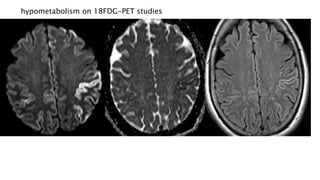

hypometabolism on 18FDG-PET studies

RADIOGRAPHIC FEATURES MRI MRI findingsmay be bilateral or unilateral and symmetric or asymmetric, and include: T2 hyperintensity obasal ganglia (putamen and caudate) othalamus ( hockey stick sign and pulvinar sign) ocortex: most common early manifestation owhite matter persistent restricted diffusion on DWI (considered the most sensitive sign) Review of sequential studies also typically demonstrates rapidly progressive cerebral atrophy.

• 52.